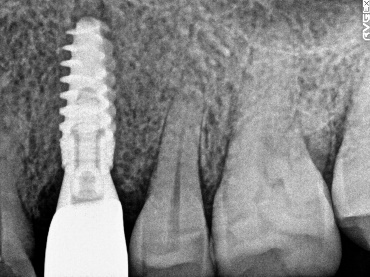

レントゲンで詳しく診てみると、虫歯が歯根のほうまで進行し、保存することができないことがわかり、抜歯しました。抜歯後、骨が大きく欠損していましたので、骨造成を行いインプラントを2本埋入しました。

所感

抜歯後の欠損したところを補う方法には、部分入れ歯、ブリッジ、インプラントがあることを説明したところ、自分の歯と同じような感覚で嚙むことができるインプラントを選択されました。この方は、2016年に右下にインプラント治療をし、インプラントの良さを十分に理解しておられましたので、今回も2本歯を失ったところにインプラント治療を希望されました。今回もX-Guideを使った埋入で、安心安全に行うことできました。

Before

【抜歯後】

After